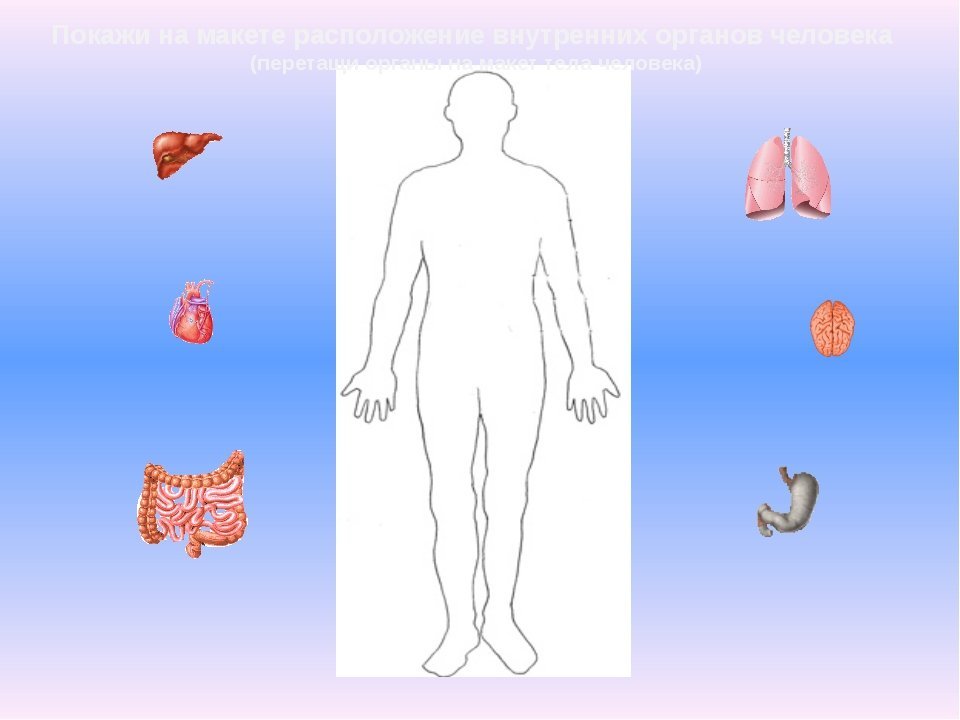

Изображения и визуализация внутренних органов человека

Раздел: Секреты мастерства